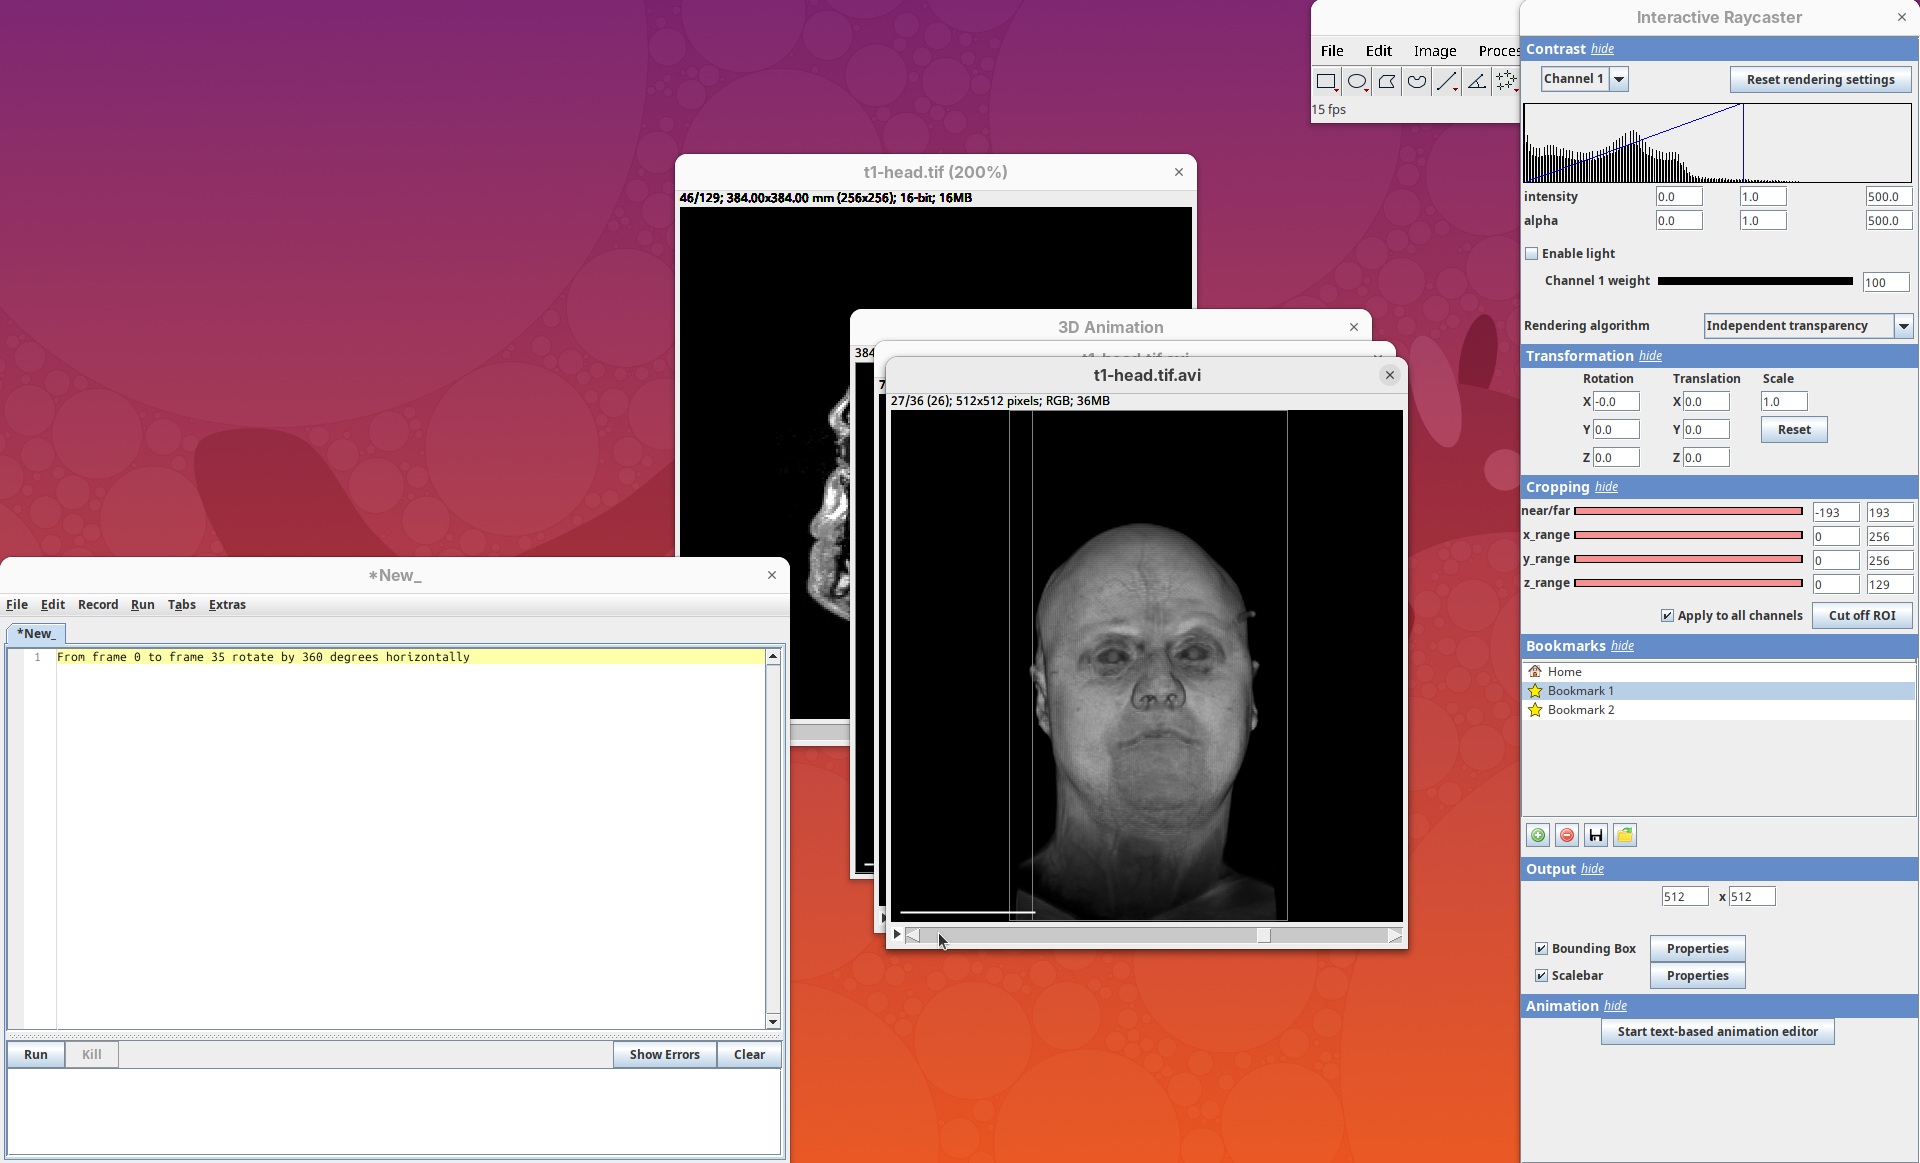

Plugins>3Dscript>Interactive Animation.

Two new windows will open: 3D Animation with the initial rendering of the data and Interactive Raycaster with all the fields to control the rendering parameters.

Animation 3D

Now that we learned the basics of setting up the rendering and view parameters, we can start generating animations of the data.

- Click on the

Animationsection and on theStart text-based animation editorbutton.

This will open a special editor window for writing the animation script.

Rotate horizontally

Let’s start with the simplest animation: a rotation of the head around 360 degrees. We need to define the number of frames that the animation will have and what will happen during these frames. We can start by defining that the animation will have ten frames.

Note: frame counting in 3Dscript begins from 0 (frame 0 to 9 has 10 frames).

The editor has a strong autocomplete; you only need to type one letter at a time to be able to write the exact text needed for the animation.

- Type

f. The editor will autocomplete withFrom frame <frame>. - Type

0and space. The autocomplete will fill withFrom frame 0 to frame <frame>. - Type

9and space. The autocomplete will show a dropdown menu with several options (rotate by,translate,zoom by a factor of,reset transformation, andchange). - Choose

rotate byand pressTab. The autocomplete will showFrom frame 0 to frame 9 rotate by <degrees>. - Type

360and space. The sentence will beFrom frame 0 to frame 9 rotate by 360 degreesand a dropdown will show the optionshorizontally,vertically, andaround. - Choose

horizontallyand on the next menu choose(none).

We have our first animation script and it’s just this single sentence:

From frame 0 to frame 9 rotate by 360 degrees horizontally- Press

Run.

A new window will show up with an image stack of 10 frames containing the generated animation.

- Press play or and watch the head turn 360 degrees during these 10 frames.

Note that we did not need to define how many degrees the head would turn for each frame. We can simply state that we need the head to turn 360 in these 10 frames and 3Dscript will deal with it.

Make it smoother

Our first animation is cool, but a bit jumpy. To make it smoother we can add more frames.

- Change the final frame from

9to35, so that the animation will have 36 frames in total.

Now each frame rotates by 1 degree and the animation is much smoother.